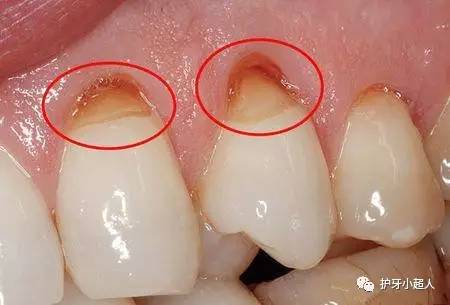

不过除了龋齿会造成牙洞,牙齿根部的楔形缺损也会导致牙洞发生。牙齿楔形受损,就是在牙齿颈部、根部位置产生缺损,形成楔子形状的缺口,以其形状而称之为牙齿楔形缺损。

造成牙齿根部楔形受损的原因主要有以下两个方面的原因:一是牙刷刷毛过硬,对牙齿的损害力强,日积月累,就会出现牙齿楔形受损;第二则是因为刷牙的方式,大部分人刷牙的方式都是横向的,而且刷牙的力度特别大,在用一部位向同一个方向持续作用力,造成牙齿楔形受损。一般来说,牙齿楔形受损是在牙齿的颈部和根部,因为这两个部位的牙釉质相对稀薄,更易受到损害。

一旦形成牙齿楔形受损,脆弱的牙根暴露,极易成为牙菌斑欺负的对象。长此以往,食物残渣在此堵塞,类似于蛀牙牙洞,刷牙很难去除,进而变质变酸,腐蚀牙齿;腐蚀从牙齿颈部开始,在此将牙齿腐蚀断裂,缺损变为整个牙冠,形成牙洞。